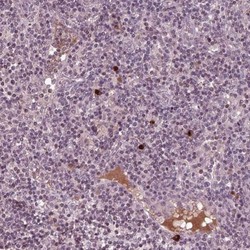

- Immunohistochemistry: Pentraxin 4 Antibody [NBP2-68966] - Staining of human lymph node shows strong cytoplamic positivity in non-germinal center cells and distinct plasma staining.